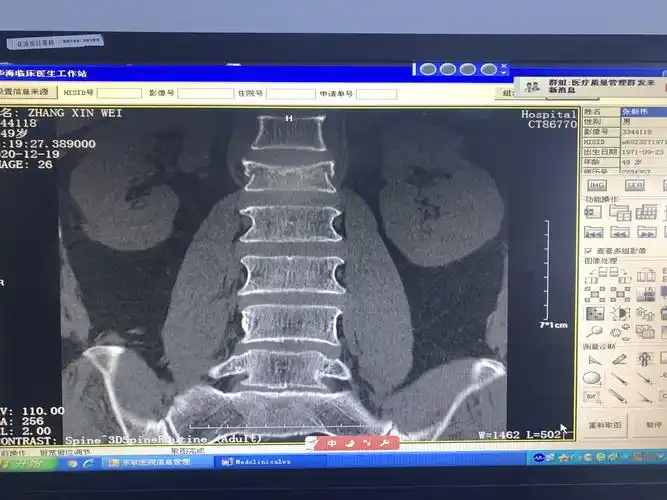

38床, 腰1椎体压缩性骨折

腰1椎体爆裂性骨折,腰1 2 3双侧横突骨折